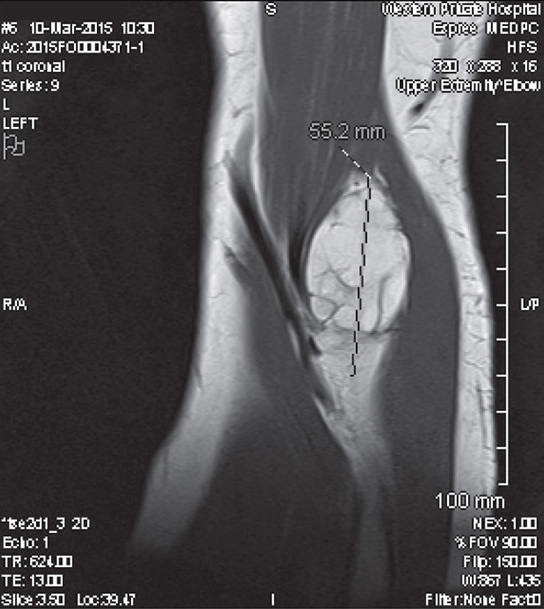

Липосаркома На Бедре Фото 117 фотографий